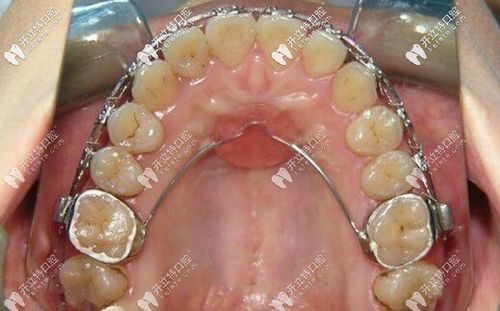

典型病例中,nance弓的应用效果可通过直观图片呈现:一位II类1分类患者拔除上颌第一前磨牙后,佩戴nance弓6个月,通过治疗前后对比可见,上颌第一磨牙无明显近中移动(磨牙间距保持稳定),而拔牙间隙内收整齐,腭托与腭部贴合良好,无黏膜刺激,图片中清晰的磨牙位置变化与腭托状态,直接反映了nance弓的支抗控制效果。